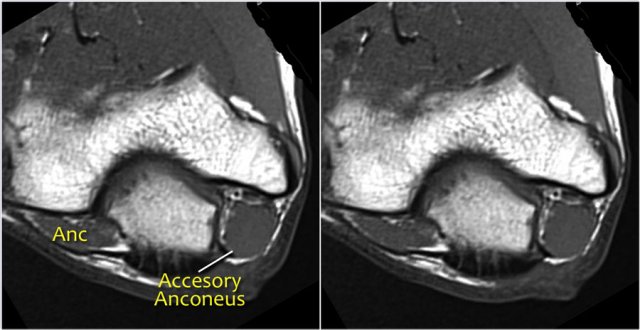

5. Muscle anomaly (eg, an accessory anconeus muscle) as is present in this case.

6. Soft-tissue mass: ganglion, lipoma, osteochondroma, synovitis secondary to rheumatoid arthritis, infection (eg, tuberculosis), and hemorrhage.